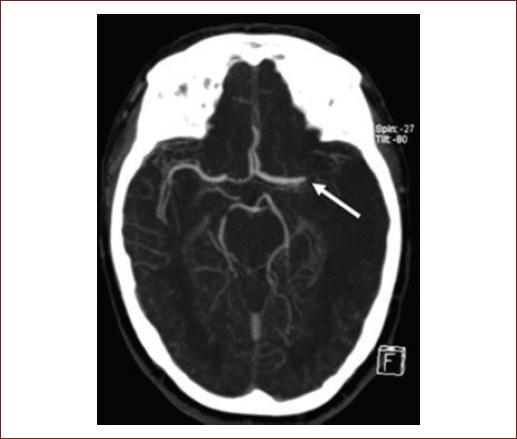

CTA

The primary modality used to assess blood vessels is CTA, which is increasingly used as part of the initial imaging protocol to identify patients with LVO. CTA is also the most frequently used vascular imaging modality in clinical trials and clinical practice. This sequence can be obtained on all modern CT scanners and can be easily incorporated into an AIS imaging protocol. It requires intravenous iodinated contrast and, depending on the equipment that is used, is usually completed within 2 min. There may be concern for the use of contrast, but the 2019 update to the AHA guidelines states that the risk of contrast-induced nephropathy is relatively low, and waiting for the laboratory results may delay treatment; this is especially true in patients with no known history of kidney disease7, and even then, according to a systematic review, neither CTA nor CTP increase the risk of acute kidney injury in patients with known chronic kidney disease33. CTA allows us to pinpoint the location, extension of the vessel occlusion, and identifying thrombi in large proximal intracranial arteries. Determining the location of the thrombus helps predict the likelihood that thrombus will respond to rtPA or MT, especially in tandem lesions (occlusions with both intracranial and extracranial components)34. An LVO will appear as an amputation (Fig. 3) or reduction of the affected vessel's caliber. It is also possible to measure thrombus length, which will influence recanalization potential, which is to say that clot length has been reported to be inversely proportional to rtPA effectiveness, especially if said clot is > 8 mm35. This is not normally used in the clinical setting and is currently not included in any guidelines.

Figure 3 Computed tomography angiography with occlusion of the left middle cerebral artery (white arrow).

CTA is also useful to determine the etiology of an ischemic stroke and to identify underlying pathologies, such as carotid atherosclerosis (artery-to-artery embolism), intracranial atherosclerosis, or arterial dissection22. Figure 3 shows a CTA with occlusion of the left MCA.